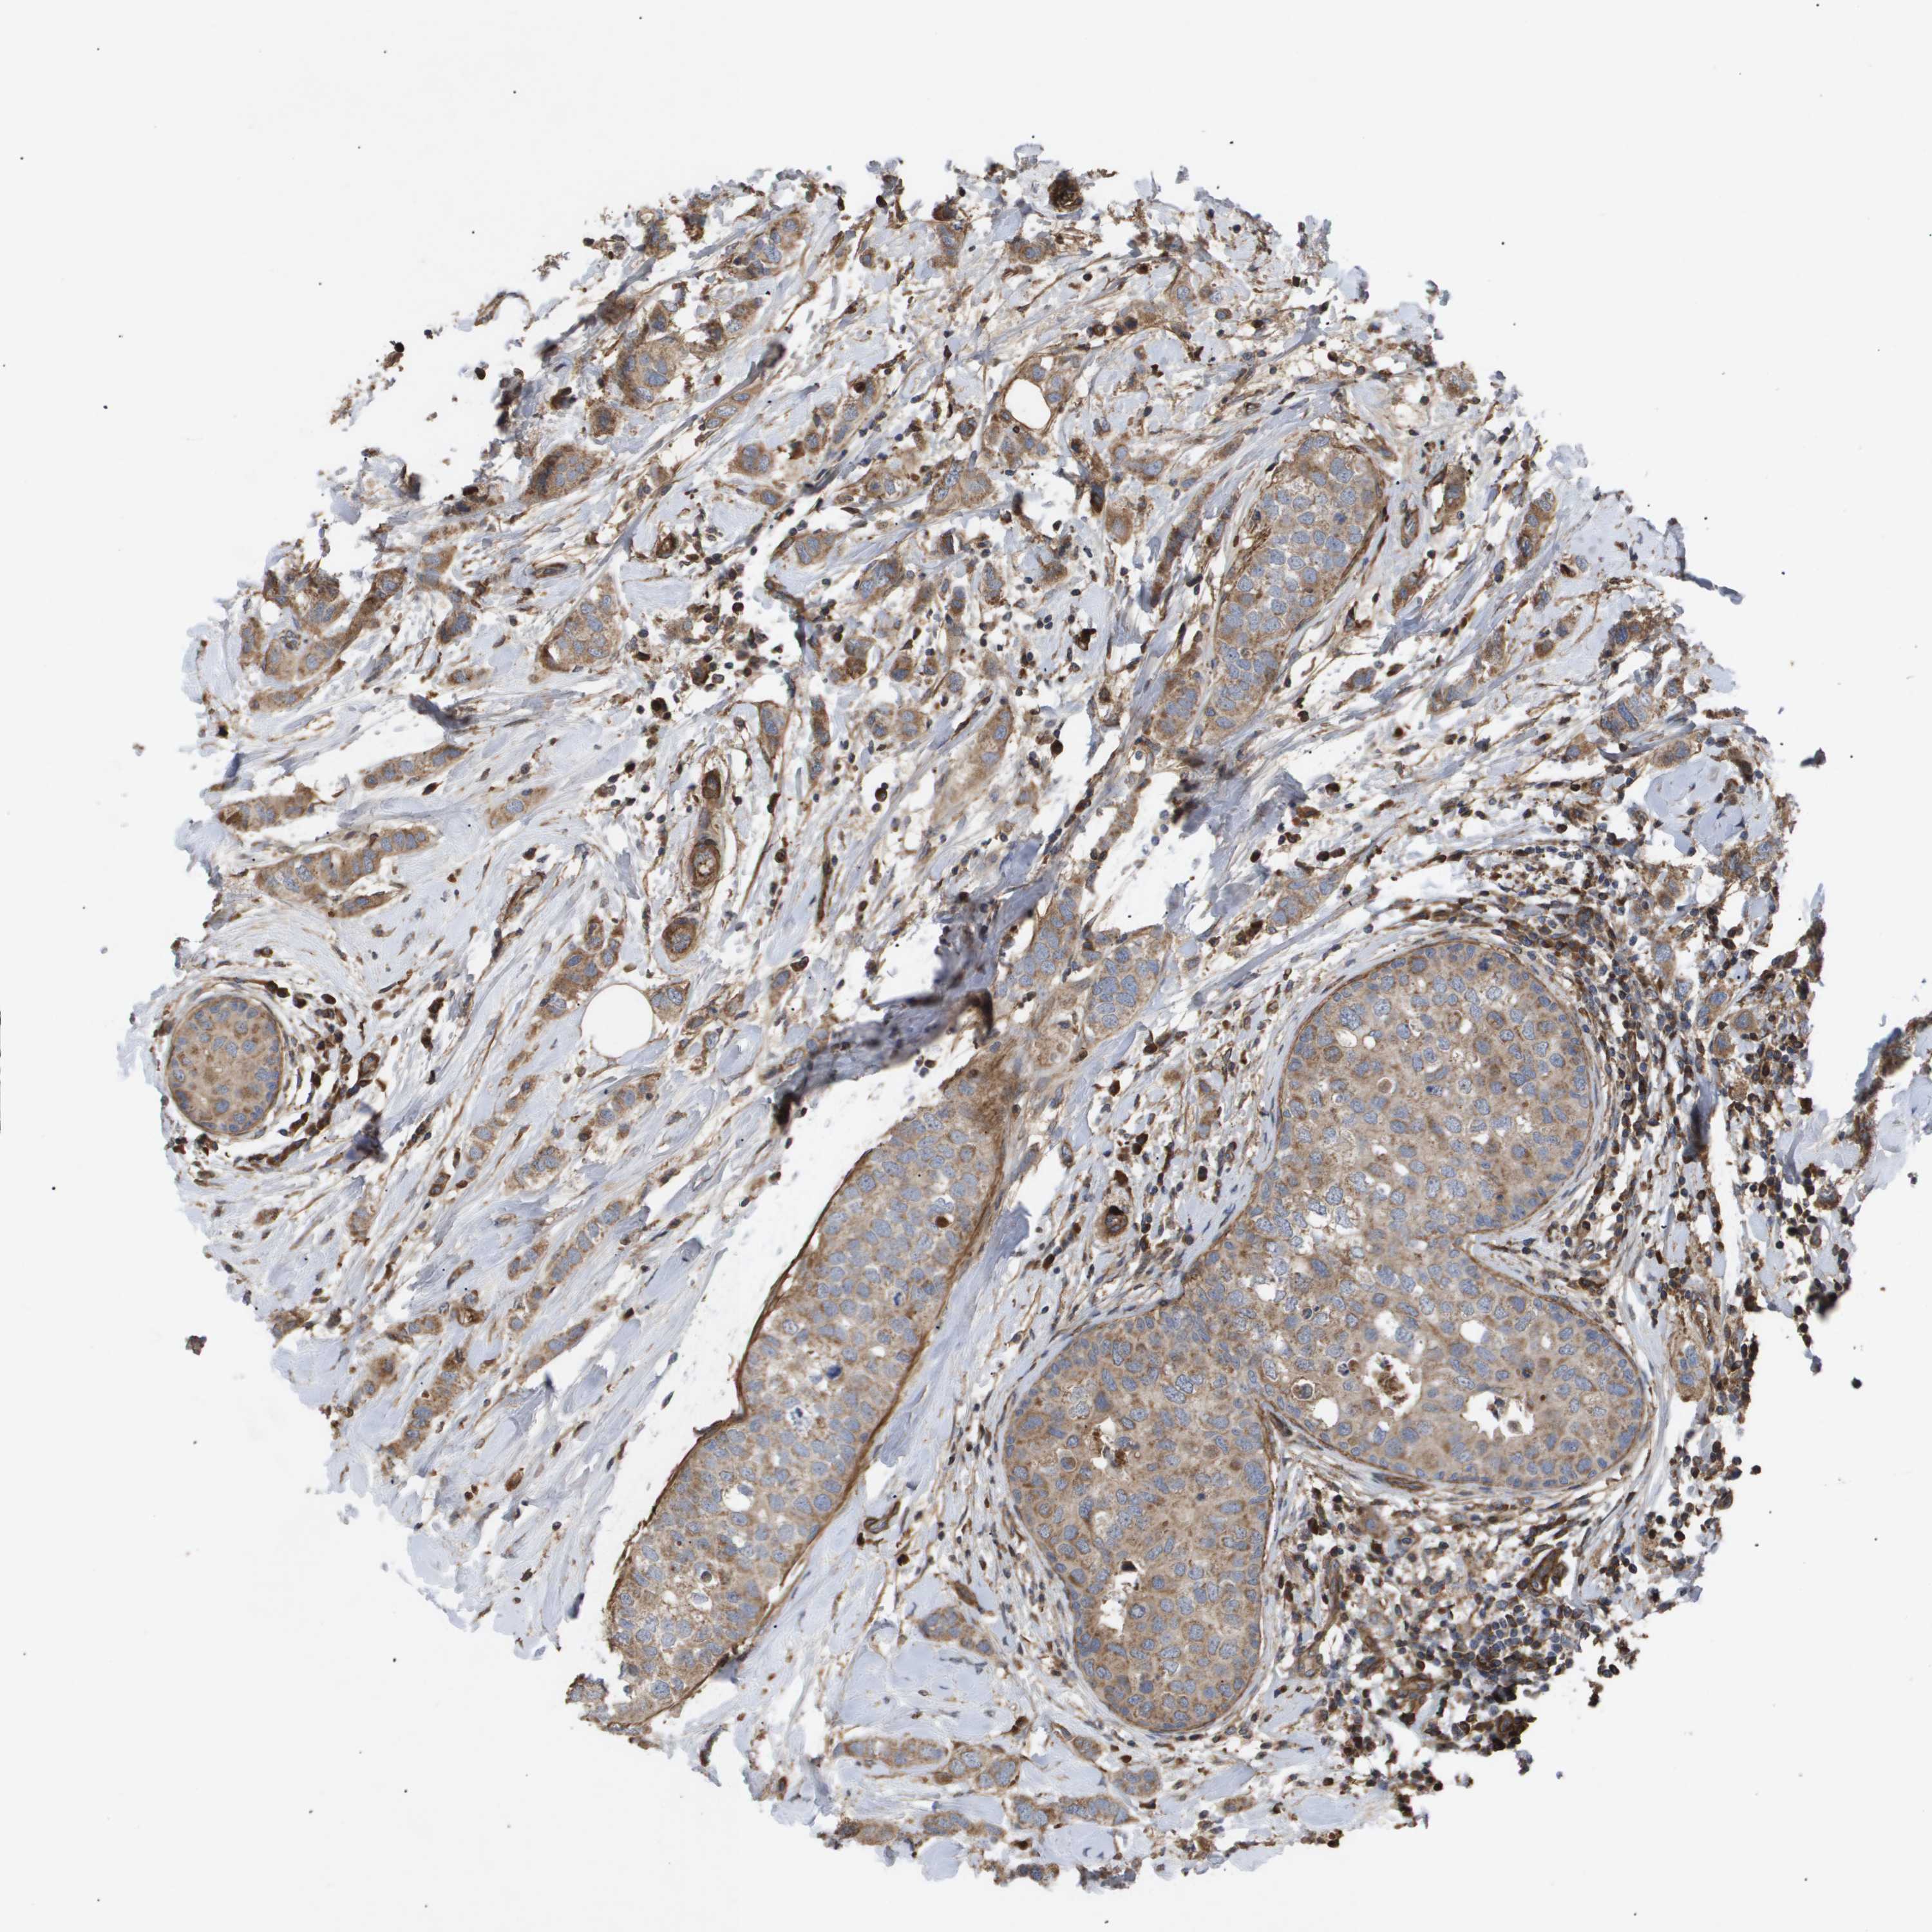

CANCER BREAST CANCER Show tissue menu

BRCA TCGA BRCA VALIDATION PROTEIN EXPRESSION